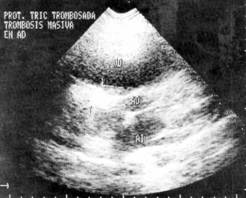

Figure

1: Trans-thoracic echocardiogram

where a tricuspid prosthesis is observed with increase in its echogenicity that

extends toward right atrium corresponding to a massive thrombosis.

and reported absence of prosthetic sounds. The transthoracic echocardio-gram

(TTE) revealed a thrombosis of the tricuspid prosthesis (increase of

echogenicity in the auricular side of the prosthesis and a marked decrease of

the movements of the disc).